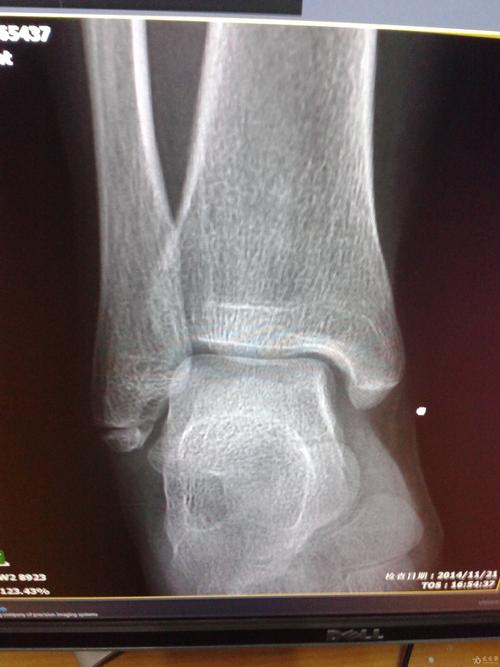

踝关节 放射科 骨伤科 x光片 如何